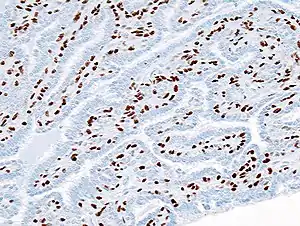

![]() Гістопатологія інтрадуктальної папіломи грудей; ексцизійна біопсія; імунозабарвлення для білка p63. Гістопатологія інтрадуктальної папіломи грудей; ексцизійна біопсія; імунозабарвлення для білка p63. | |

Гістопатологія внутрішньопротокової папіломи молочної залози шляхом ексцизійної біопсії. Забарвлення гематоксиліном та еозином.

Гістопатологія внутрішньопротокової папіломи молочної залози шляхом ексцизійної біопсії. Імунозабарвлення для альфа-актину гладкої мускулатури.